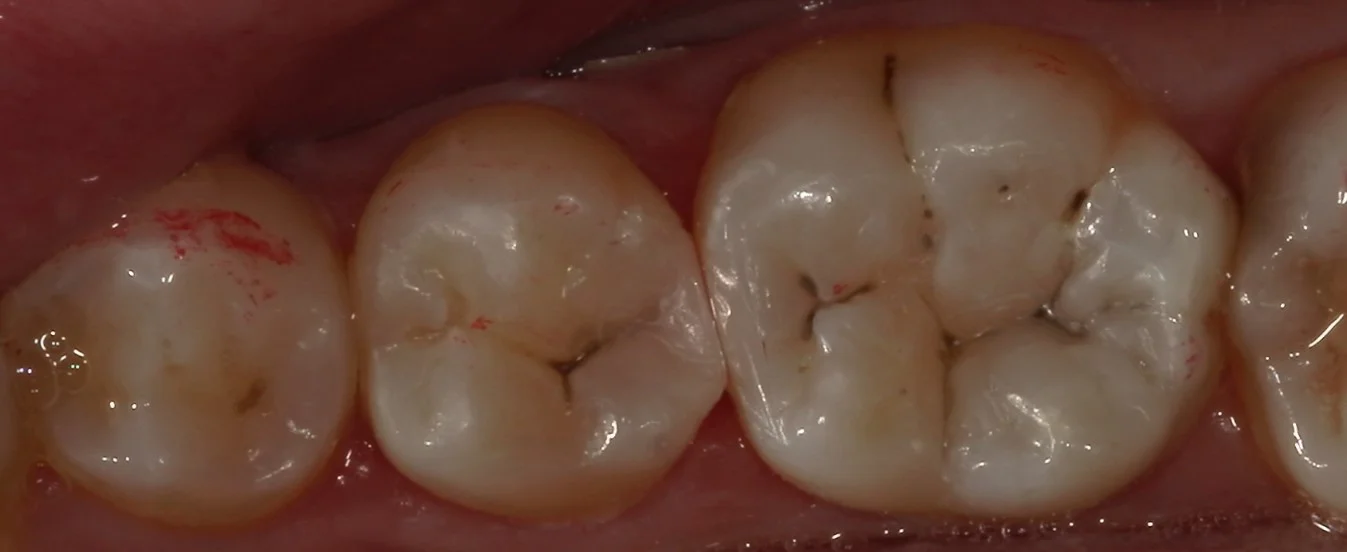

虫歯をとりきったのがこちらの写真になります。

黒い部分が残っていますが、こちらは虫歯を染め出す液にも染色されませんし、十分な硬さがある部分になります。

本来は綺麗に詰めるためには可及的に除去しておいた方が有利なのですが・・・

今回は痛みが途中で出てしまったため、そこまでは除去せずに、取れる範囲で着色を除去しました。

そして、詰め終わったのがこちらです。

歯の底の色を隠すように色を消せる材料を使用しながら詰めました。

歯の溝の色を本来の色に合わせて詰めましたので、違和感はなく仕上げられたかと思います。 歯との間の部分にもフロスを通しても引っ掛かりは一切ない状態に仕上げているので、問題なく使用して頂けるかと思います。 患者さんは歯科医師なので、色合わせなどの難しさも十分承知の方でしたので、非常に喜んでいただきました。